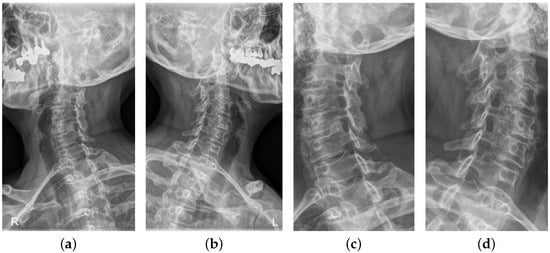

After HE, the bone area becomes brighter in the X-ray image, while the dark area other than the bone area becomes darker so that the contrast becomes more distinct, as shown in Figure 3. As a result, the foramen, an important feature to detect foraminal stenosis, becomes further clarified. In this study, the input X-ray images are first preprocessed to obtain the ROI-cropped images, followed by histogram equalization.

The ablation study results confirm that the proposed performance enhancement methods, i.e., HE, Flip, and STN, have a positive effect on the performance of the proposed model, as can be observed by comparing the data in Table 4 and Table 5. First, agreeing with the previous studies using X-ray data, an ablation experiment was performed to confirm whether it is effective to apply Histogram Equalization. The result of Histogram Equalization is shown in Figure 3, and the results of training the model using the data to which HE is applied are presented in Table 5. According to Table 5, the performance was better in most metrics than in non-histogram equalization applied data, as this study predicted. In the case of the right oblique view, the accuracy increased by approximately 3%, and in the case of the left oblique view, all metrics increased except specificity. In the left oblique view, the accuracy increased by approximately 1%, the F1 score increased by approximately 3%, and sensitivity increased by approximately 5%.

Figure 3. Results of Histogram Equalization. (a) right ROI cropped oblique view, (b) left ROI cropped oblique view, (c) right ROI cropped oblique view with HE applied, and (d) left ROI cropped oblique view with HE applied.